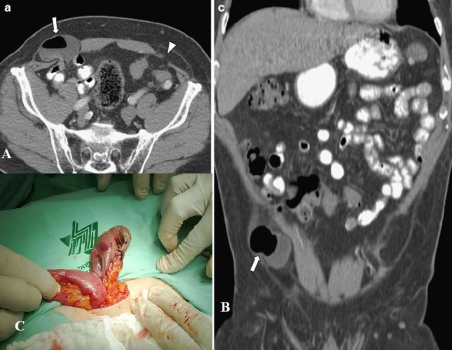

Hình 20: Bệnh nhân nữ 70 tuổi nhập viện vì đau bụng nôn ói. Hình CT thấy cấu trúc hình ống bắt quang thành ở trong ống đùi phải được nhận định là ruột thừa(mũi tên), các quai ruột non dãn lớn. Sau phẫu thuật: hồi tràng và túi thừa Meckel cách van hồi manh tràng 60 cm, ruột thừa và manh tràng thoái vị vào trong ống đùi phải. Túi thừa Meckel bị dò tạo ổ abscess kèm ruột thừa viêm trong ống đùi phải. (A. W. Phillips · S. R. Aspinall. CASE REPORT. Appendicitis and Meckel’s diverticulum in a femoral hernia: simultaneous De Garengeot and Littre’s hernia. Springer Published online 27 march 2011).

Thoát vị Spigelian : thoát vị qua nếp bán nguyệt của cân cơ Spigelian, là nơi các cân cơ thành bụng trước bên hợp nhất lại để tạo thành bao cơ thẳng bụng. Thoát vị này hầu như xảy ra ở nơi đường cung bắt chéo nếp bán nguyệt và ở trên động mạch thượng vị dưới. Túi thừa Meckel có thể bị thoát vị qua đây.

Hình 22: Thoát vị Spigelian hai bên. A, Túi thừa Meckel (mũi tên)và mạc nối (đầu mũi tên) trong thoái vị Spigelian. B, CT Coronal tái tạo, túi thừa Meckel trong thoát vị Spigelian. C, Túi thừa Meckel bị nghẹt trong thoát vị Spigelian xuất huyết và hoại tử.

(Abdel-Rauf Zeina et al (2012). Computed Tomographic Diagnosis of Incarcerated Meckel’s Diverticulum in a Patient with Bilateral Spigelian Hernia. J Gastrointest Surg 16:448)